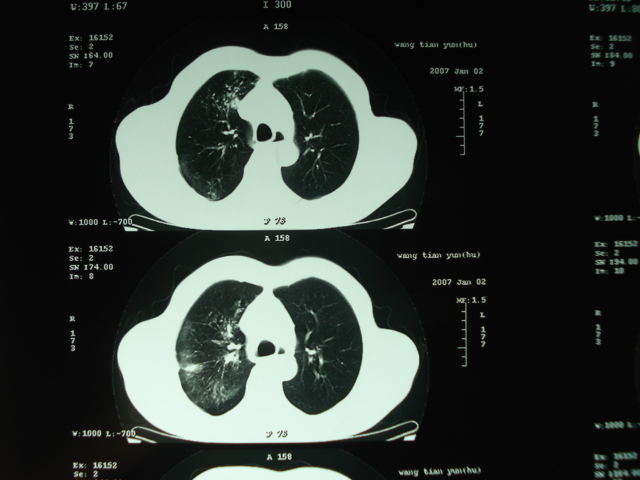

以下是引用狙击手在2007-4-18 20:17:00的发言:[br]原:2007/1/22号ct片:右肺上叶可见片状、云雾状高密度影,右肺上叶后段可见三角形高密度影,尖端指向肺门,右肺上叶后段支气管壁不规则增厚,管腔不规则增厚,纵隔未见肿大淋巴结.[br] 今ct:右肺上叶片状影增大,右肺上叶后段不张及右肺上叶后段支气管壁不规则增厚未见变化,右肺下叶背段支气管壁不规则增厚.[br] 如果考虑肺结核,但从临床证据看竟然没有一项支持肺结核,不知患者是否已经过正规抗结核治疗。没有的话,3个月了前后片看起来变化不大,似乎有不太符合肿瘤征象,不知患者是否抗炎治疗过,下叶支气管增粗还是要高度警惕,同意楼主意见,将常规病理,生化检查再做一遍。[br]

以下是引用狙击手在2007-4-18 20:17:00的发言:[br]原:2007/1/22号ct片:右肺上叶可见片状、云雾状高密度影,右肺上叶后段可见三角形高密度影,尖端指向肺门,右肺上叶后段支气管壁不规则增厚,管腔不规则增厚,纵隔未见肿大淋巴结.[br] 今ct:右肺上叶片状影增大,右肺上叶后段不张及右肺上叶后段支气管壁不规则增厚未见变化,右肺下叶背段支气管壁不规则增厚.[br] 如果考虑肺结核,但从临床证据看竟然没有一项支持肺结核,不知患者是否已经过正规抗结核治疗。没有的话,3个月了前后片看起来变化不大,似乎有不太符合肿瘤征象,不知患者是否抗炎治疗过,下叶支气管增粗还是要高度警惕,同意楼主意见,将常规病理,生化检查在做一遍。[br]